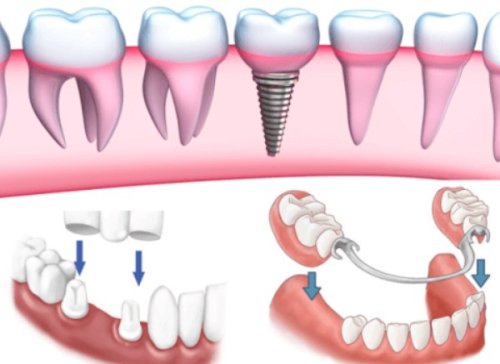

Có 3 khoa học trồng răng kém chất lượng đó là hàm giả tháo lắp, tiến hành cầu răng sứ và cấy ghép implant. Mỗi phương pháp đều có những ưu, sai sót riêng phù hợp với hiện trạng mất răng của người bệnh. Trong đó, cấy ghép implant được xem là Hiện đại nhất, người bệnh sẽ được chuyên gia cấy trụ implant vào bên trong, sau một giai đoạn khi trụ implant đã phù hợp vào trong xương hàm thì mới tiến hành lắp răng bên trong. Thầy thuốc cũng sẽ xếp đặt răng đều đặn nhất, cố định nhất để không có sự chuyển dịch thực hiện lệch nào có thể diễn ra, để người bệnh không nhất thiết mất công đi niềng khi thấy hàm răng không được không ngừng.

nếu như người bệnh trồng răng sứ cả hàm thì nên cân nhắc đến chuyện có nên đi niềng răng hay không, bởi trước khi trồng thì Y Bác sĩ đã xếp và cố định đều răng nên bạn không mong muốn cần thiết đi niềng. Đặc biệt là đối với thực hiện cầu răng sứ và cấy ghép implant, răng lúc này đã được cố định chắc chắn vào trong xuong hàm nên chẳng thể tháo rời hay chuyển dịch đi. Vậy nên, niềng răng sẽ không đem lại công hiệu cao đối với hai hiện tượng này.